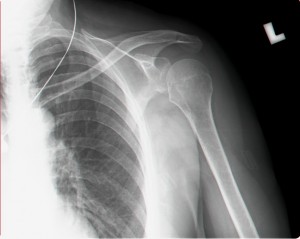

נ.מ אחרי טיפול בגלי הלם:

כתף קפואה - גלי הלם                כאב בכתף